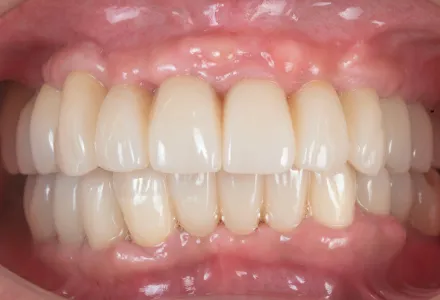

全顎治療症例2

Before

After

- 治療名

- インプラント治療+セラミックの詰め物

- 患者さん

- 70代 女性

- 執刀医

- 田中院長

- 治療

内容 - 今回はインプラント治療とセラミック詰め物を組み合わせて前歯の審美回復を行いました。歯と歯茎のラインまで自然に整えることで、機能面の改善に加えて美しい口元を実現しました。患者様から「仕上がりが非常に自然で、治療前に感じていたコンプレックスが解消されました」とのお声をいただきました。

- 治療期間

- 5ヶ月

- 治療費

- 4,500,000円〜

- リスク

- 外科処置を伴うため、術後の腫れ・痛み・内出血が生じることがあります。

また、強い力が加わると、セラミックが欠けたり割れたりする場合があります。